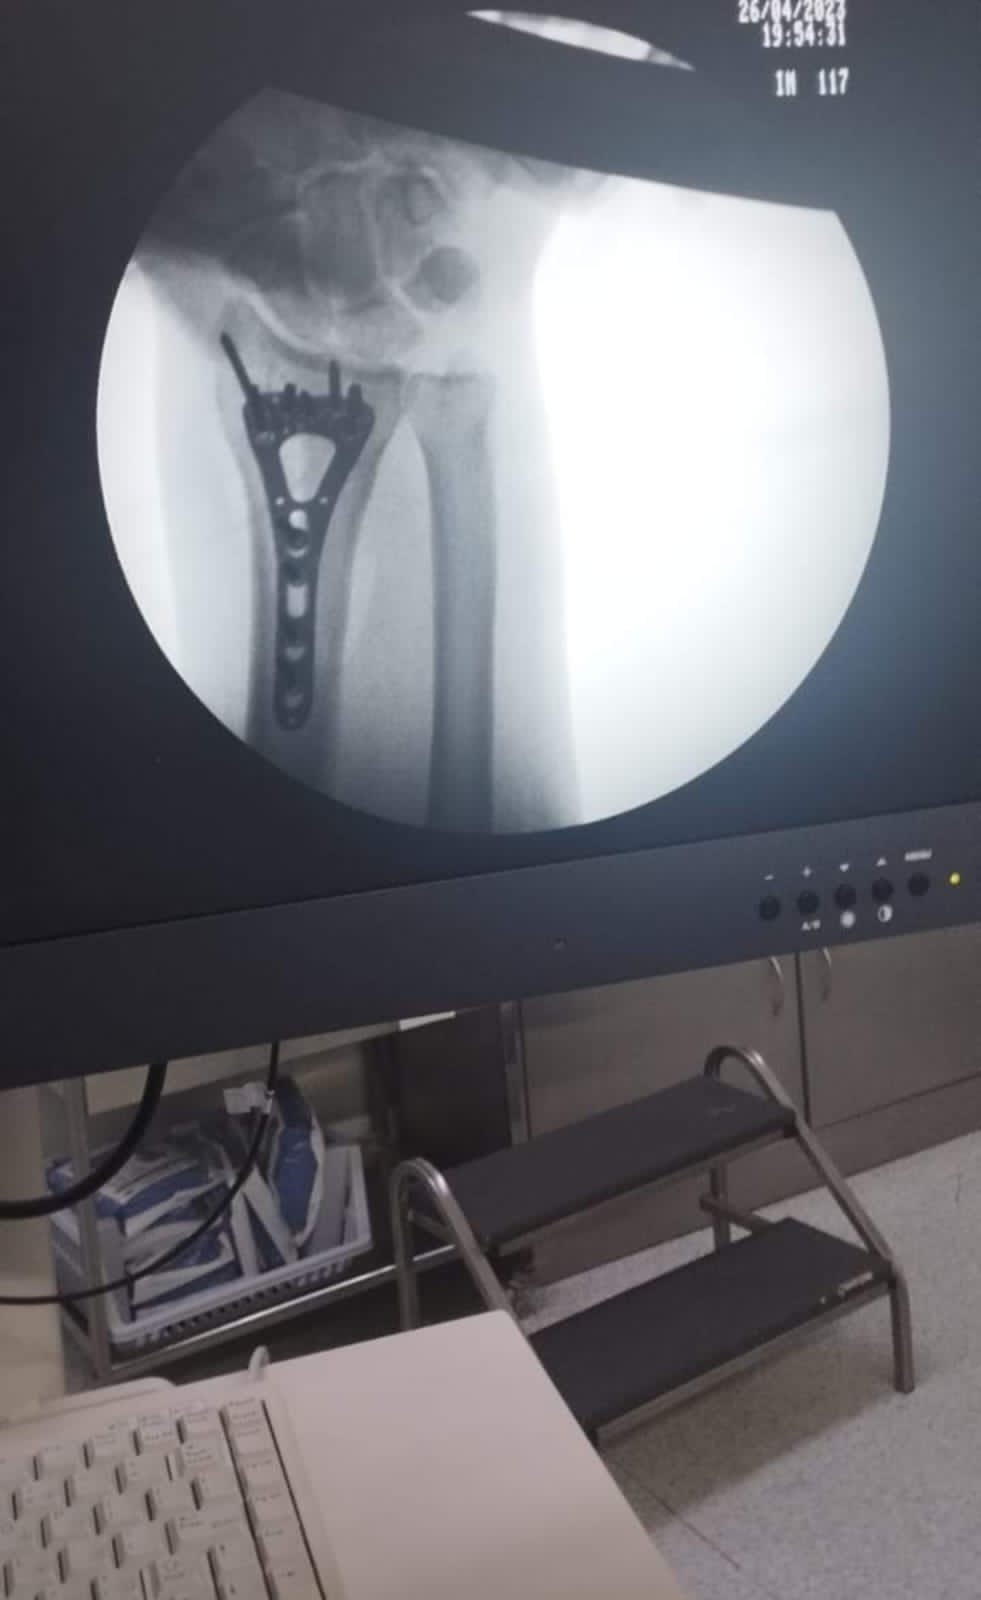

وطنا اليوم -  يقوم بعمليات تثبيت الكسور المعقدة بشكل طاريء وتبديل المفاصل بشكل مبرمج  مما خفف على المواطنين البحث عن أسرة في مستشفيات مركزية رغم صعوبة عمليات العظام من الناحية التقنية في المستشفيات النائية  إضافة الى  استقبال اعداد كبيرة بالعيادات ومعالجة جميع المرضى بالطرق المثلى انه الدكتور الانسان البارع والمتميز يزيد البريزات طبيب العظام في مستشفى الاميرة سلمى / ذيبان عيادة العظام  علماً بأنه كان  مستشفى تحويلي منذ تاسيسه والدكتور البربزات وقبل اربع سنوات في عام 2020  منذ انتقاله للمستشفى يقوم بهذه العمليات ومن بينها  عمليات نوعية لمرضى يعانون من كسور معقدة في الترقوة واجراء عمليات دقيقة ومعقدة لكسور لمرضى في مختلف أنحاء الجسم وعمليات تثبيت الكسور المعقدة وتركيب المفاصل وغيرها الكثير  والديسك " وآلامه وتبعاته وعلاجه وإجراء عمليات معقده وصعبه.

وأجرى الدكتور البريزات عمليات كبرى في جراحة العظام والتي تحتاج إلى مراكز متقدمة ومتطورة. وكذلك العمل على تثبيت أغلب انواع الكسور بطريقة طارئة وتبديل المفاصل بطريقة مبرمجة بما يتناسب مع امكانات المستشفى والتي هي  جزء من  العمليات الدورية بمستشفى الاميرة سلمى في ذيبان  والتي تخفف العبئ على المستشفيات المركزية وعلى المواطن في آن واحد.